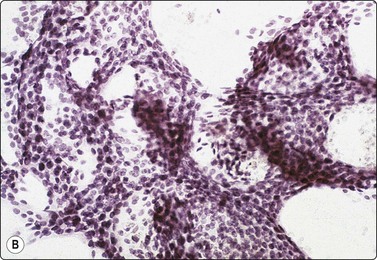

image image

Fig. 7.2 Non-neoplastic glandular breast tissue and low-grade duct carcinoma

Low-power view; (A) Bimodal population of epithelial sheets and single bipolar nuclei of non-neoplastic glandular breast tissue; (B) Single population of epithelial cells in low-grade carcinoma (MGG, LP).

Fig. 7.3 Non-neoplastic glandular breast tissue and low-grade duct carcinoma

High-power view, air-dried smears; (A) Non-neoplastic glandular breast tissue; (B) Low-grade duct carcinoma. Note single bipolar nuclei in A, and absence of bipolar nuclei, relatively mild nuclear atypia and some loss of cohesion of malignant cells in B (MGG, HP).

Fig. 7.4 Non-neoplastic glandular breast tissue and low-grade duct carcinoma

High-power view, Pap-stained smears; (A) Bimodal population in smear from non-neoplastic breast; (B) Single and clustered cells in low-grade carcinoma; some single cells probably stromal (Pap, HP).